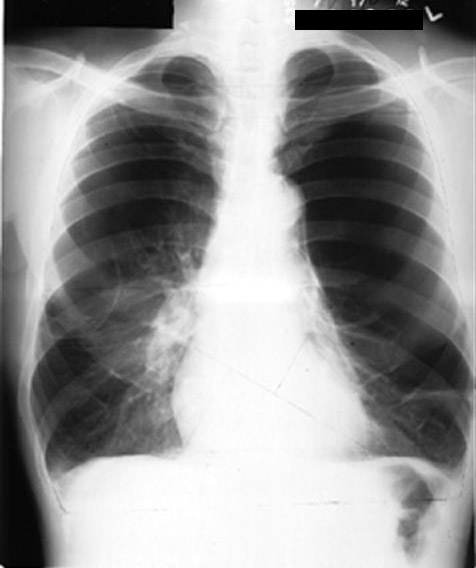

Emphysema

• Hyperlucent lung fields

• Multiple blebs

• Avascular zones

• Prominent pulmonary arteries

• Radiologic TLC

See lateral view below.